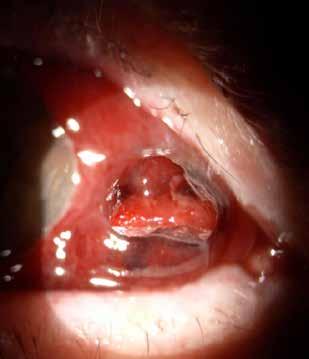

Figure 7. Multimodal imaging of Type 2 macular neovascularization secondary to choroidal rupture. Blue autofluorescence (A) and infrared reflectance (B) showing the linear change in the retinal pigment epithelium. Optical coherence tomography angiography (C) displaying the choroidal rupture as a regular line of severe choriocapillary rarefaction and a well-defined neovascular network (open arrowheads). Optical coherence tomography (D and E) revealing the rupture of retinal pigment epithelium, Bruch’s membrane and choriocapillaris with subretinal hyperreflective material and subretinal fluid cystoid space.

follows the spatial profile of the choroidal rupture, although in some cases, MNV originates from the rupture and grows laterally without specific correlation to the shape of the Bruch’s membrane break.38 (Figure 7) Similarly, patients with angioid streaks are predisposed to developing MNV. (Figure 8) Angioid streaks appear as irregular, bilateral, narrow, and jagged lines extending from the margin of the optic disc. They result from crack-like breaks in Bruch’s membrane, which is structurally abnormal, making these areas prone to localized ruptures. This process may occur spontaneously or could be secondary to even mild blunt trauma.39 The incidence of MNV ranges from 42% to 86%, and it can manifest bilaterally, often asymmetrically, in up to 71% of cases.40 Higher percentages of MNV have been found in larger and longer lesions, with even higher risk of development when the streaks are located within one disc diameter from the center of the posterior pole.41 MNV in angioid streaks is characterized by frequent recurrence in fact, even after years of inactive disease, new neovascular lesions can arise from a pre-existing lesion or as new area of neovascularization distant from the original lesion.39